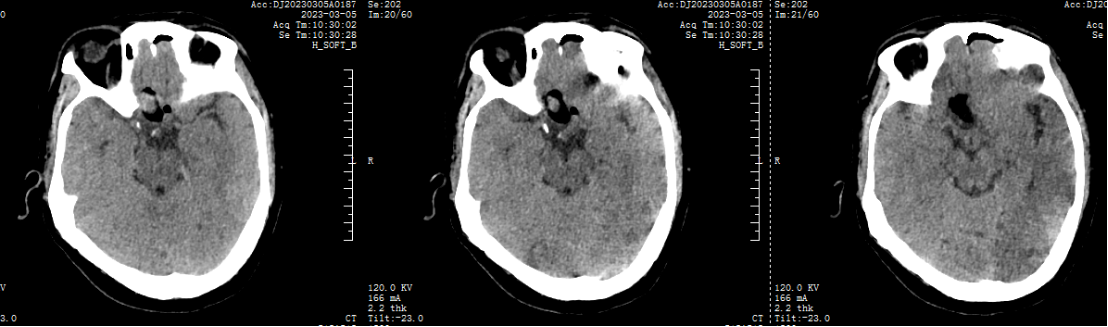

2.两天前患者无诱因出现头晕,伴恶心、呕吐、右眼视物模糊,无意识障碍,无发热、咳嗽、咳痰,无耳鸣、听力下降,无言语不清、饮水呛咳、吞咽困难,无颈强直,无肢体感觉及活动障碍等伴随症状,于我院门诊就行头颅CT示:腔隙性脑梗死,现为进一步诊治,遂来我院。

术后CT